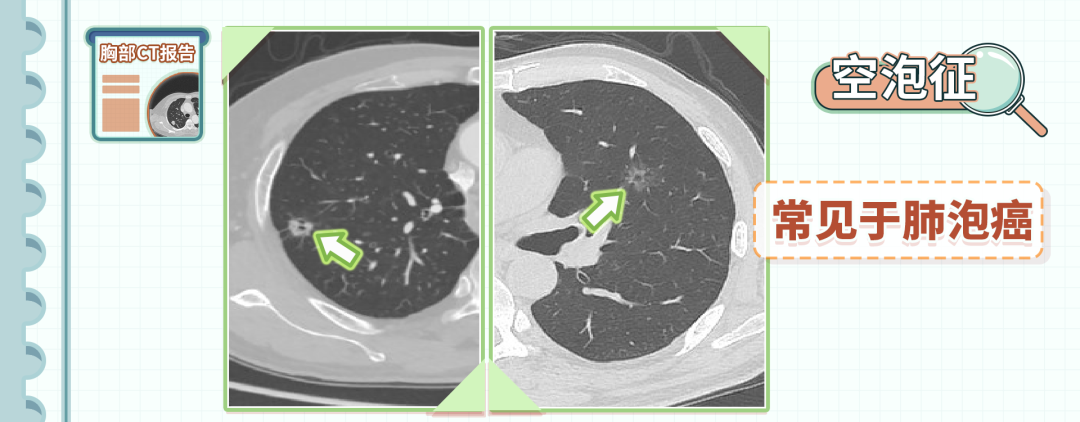

6、空泡征

空泡征是指在结节里可以看到1-2mm大小、低密度含气的影像。

这种影像多是由于未闭的支气管造成的,常见于肺泡癌。